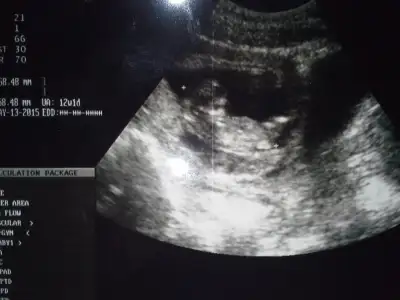

canim kanama alani ne kadarmis?.. Ne dedi doktor.. Bende de vardi 2.5 cm.. Seninki daha kucuk gozuktu bana..

boyutunu söylemedi canım,çok dedi sadece.Bu ultrasom resminde kesenin yanındaki dimi,kesenin yarısı kadar galiba,resimden anlayamadım

,orda ekrandada görüntü çok gidip geliyordu